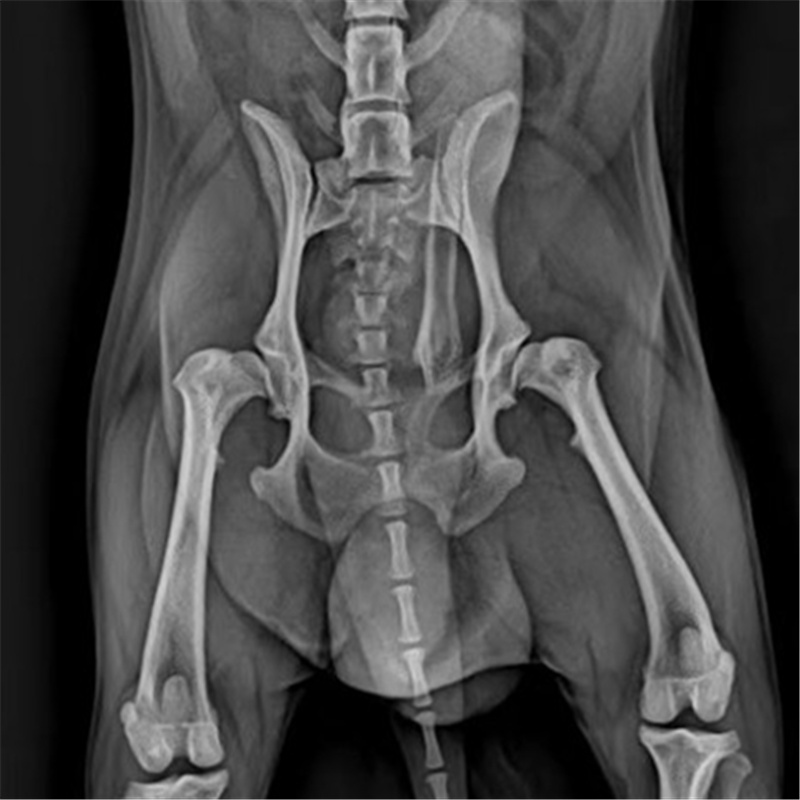

7个月大的雄性金毛犬,自5月龄起便表现出严重的运动功能障碍,出现典型的“兔跳”步态,起立与行走困难。此前辗转多家医院,髋关节发育不良的问题始终未能得到有效解决。

经系统影像学检查,刘玉龙医生确诊其为严重的双侧髋关节发育不良。考虑到患犬年龄小、病情重,若仅采取保守治疗或股骨头切除术,将无法逆转其进行性关节退化与功能障碍。在与主人充分沟通后,刘玉龙医生决定为其施行双侧髋关节置换术,从根本上重建髋关节结构与功能。

该病例的难点不仅在于患犬骨骼尚未完全发育成熟,手术精度要求极高;更在于双侧置换对手术规划、麻醉管理及术后康复都提出了系统性挑战。刘玉龙医生凭借丰富的关节外科经验,制定了分期手术方案,通过精确的假体选择与植入,成功恢复了患犬双侧髋关节的力学支撑与活动能力。术后患犬恢复顺利,运动功能显著改善,步态趋于正常,生活品质得到根本性提升。

刘玉龙医生强调,对于金毛等髋关节疾病高发品种,应从小控制体重、补充关节营养,并定期进行骨科体检,以实现早期预防与干预。该病例也证明,对于严重的髋关节发育不良,在专业团队支持下实施关节置换术,是重建运动能力、改善长期预后的有效途径。